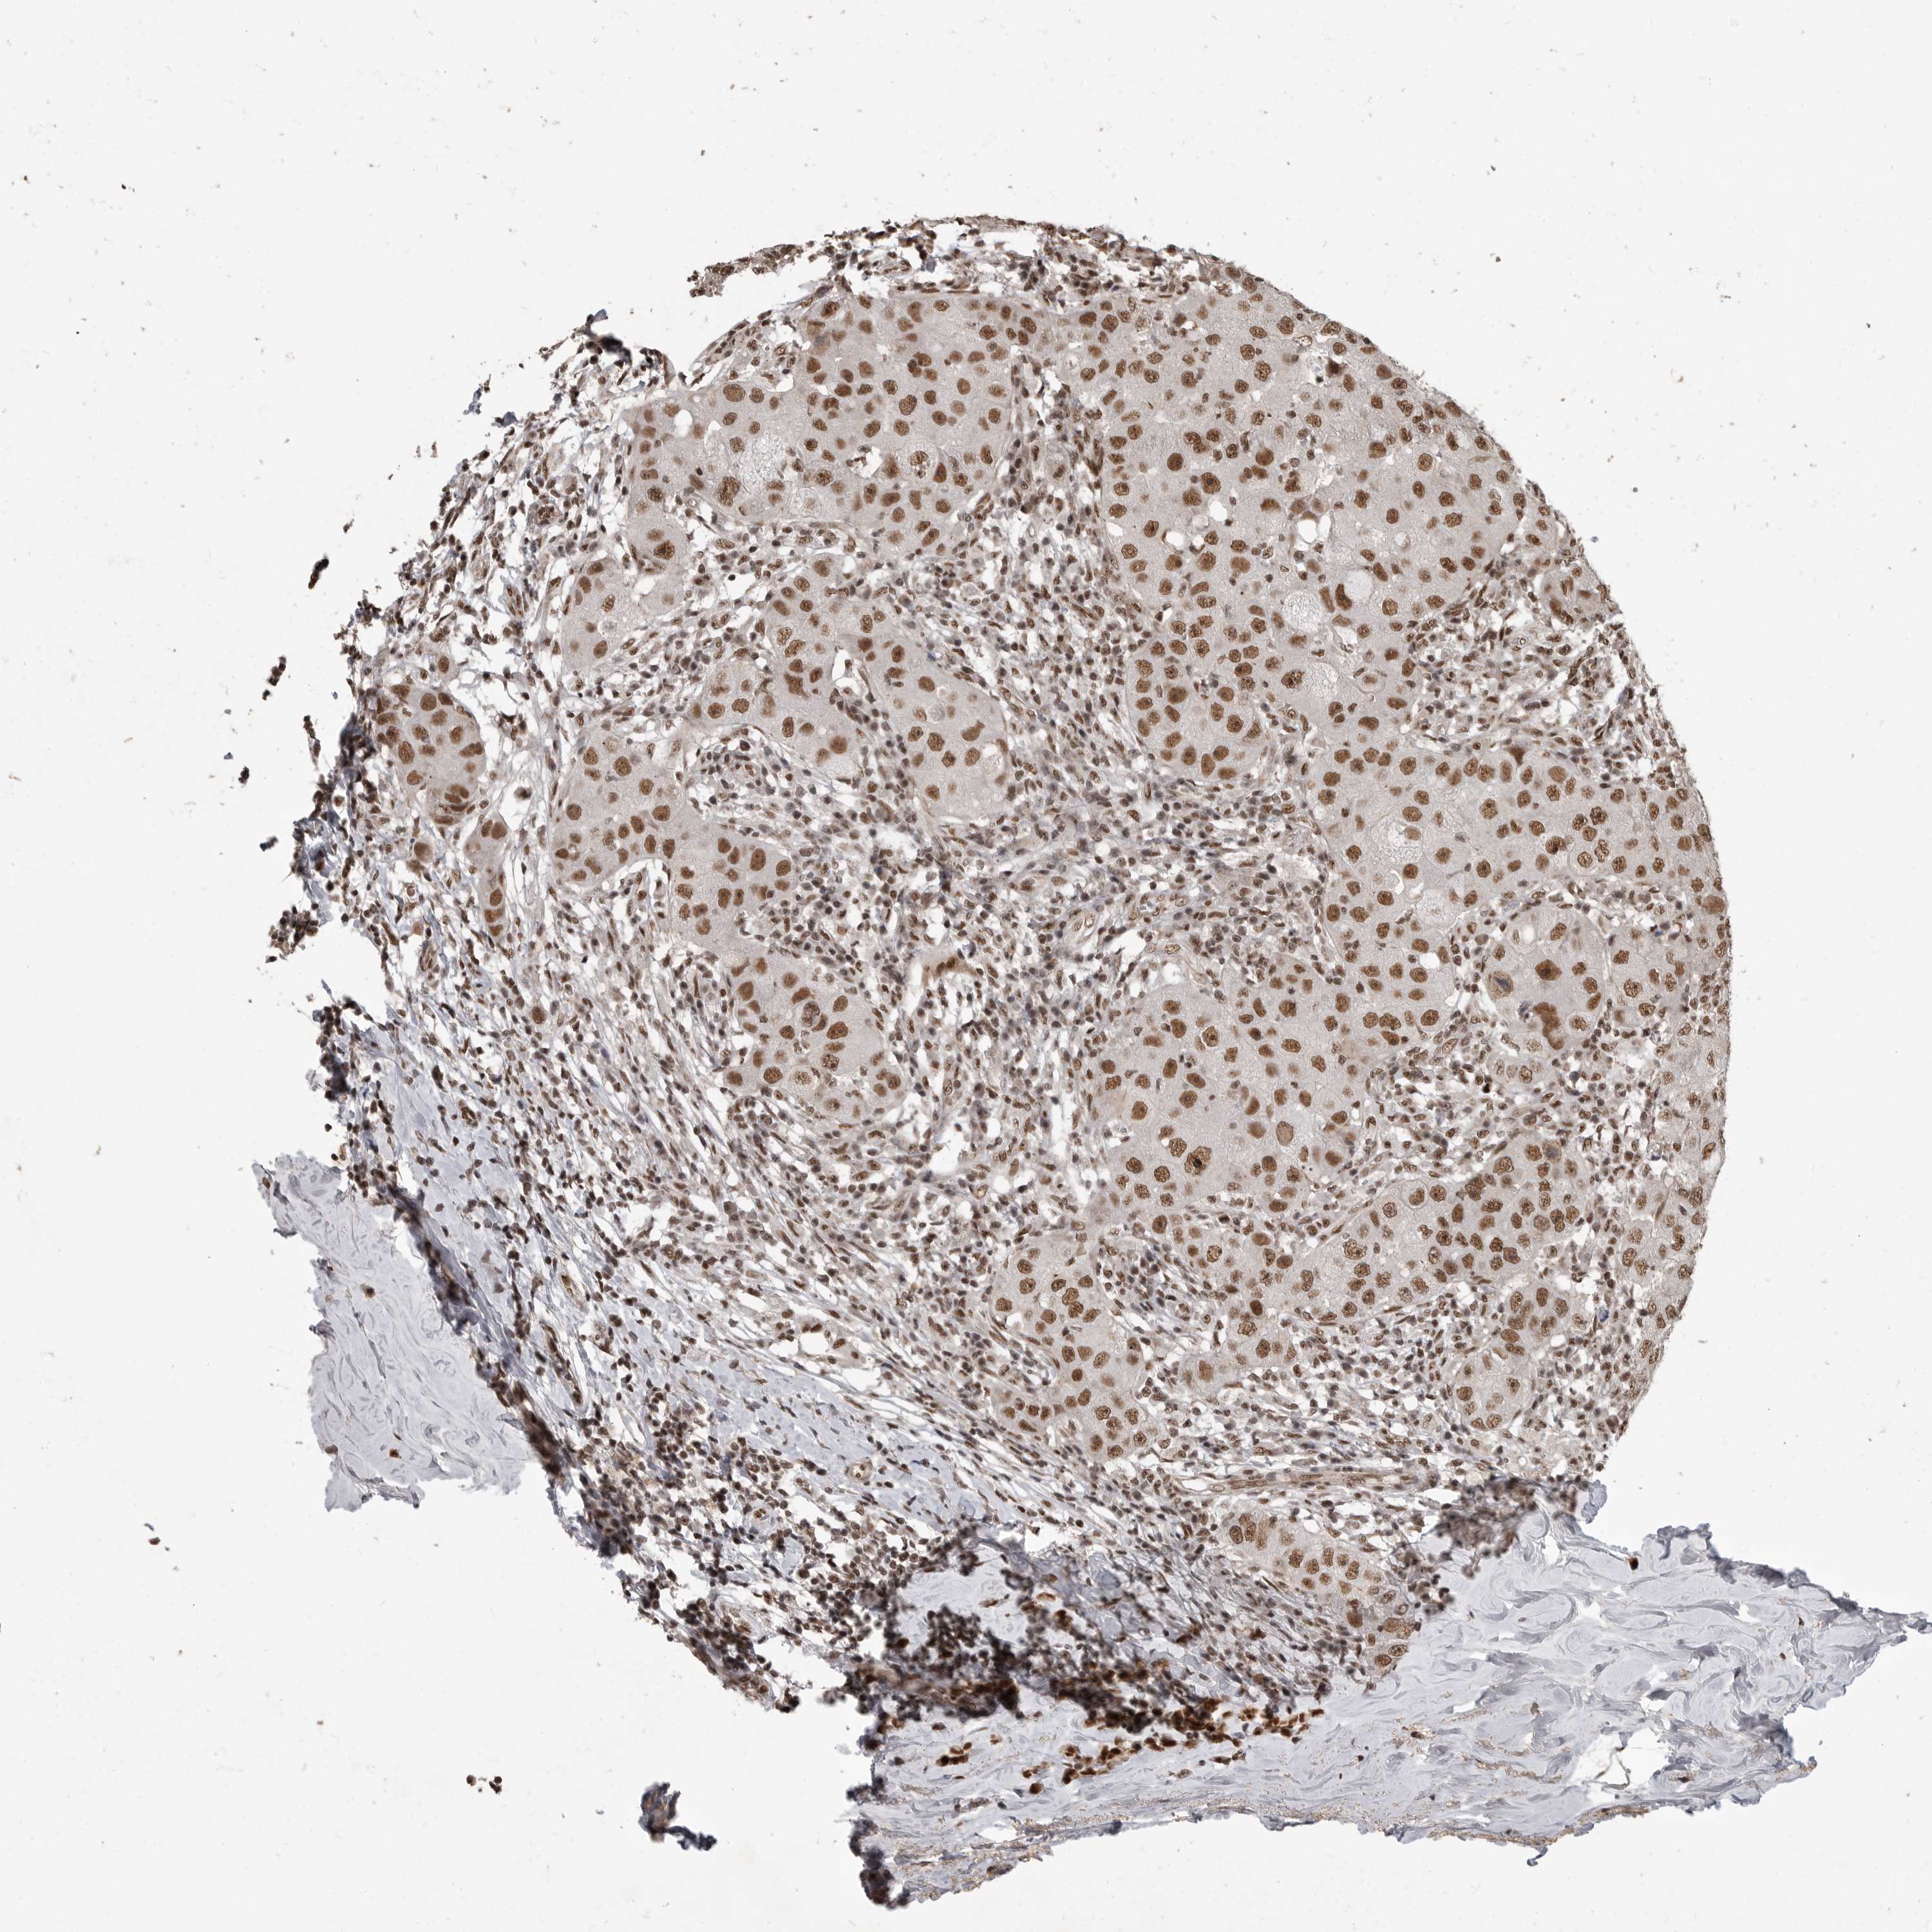

CANCER BREAST CANCER Show tissue menu

BRCA TCGA BRCA VALIDATION PROTEIN EXPRESSION